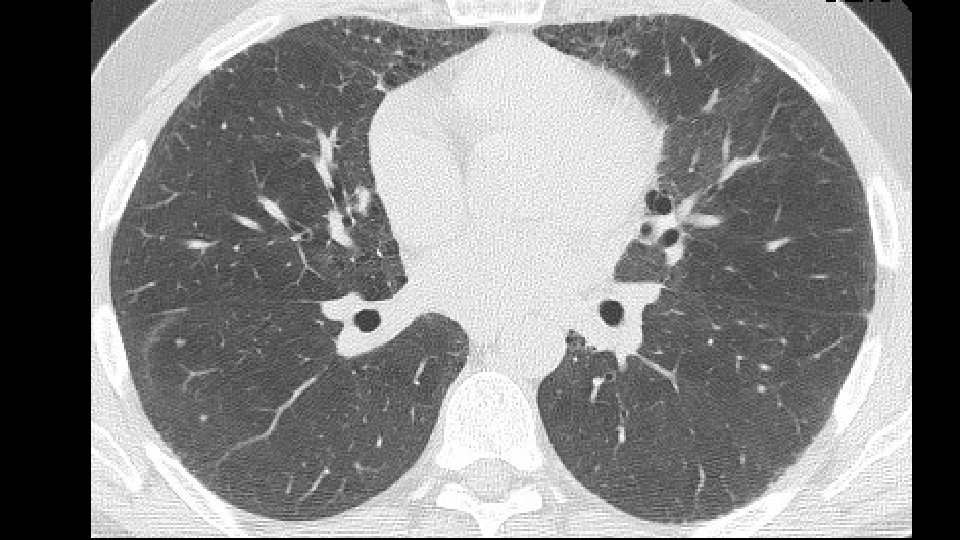

43 years old, male non smoker Co-morbidities: psoriasis, gastritis with Helicobacter History of two years of dyspnea on exertion Lab tests: no autoimmunity

Bronchovascular ground glass attenuation + subpleural sparing D. D. f. NSIP vs inconsistent UIP (GG and bronchovascular distribution)

Patients underwent transbronchial lung biopsy with cryoprobe